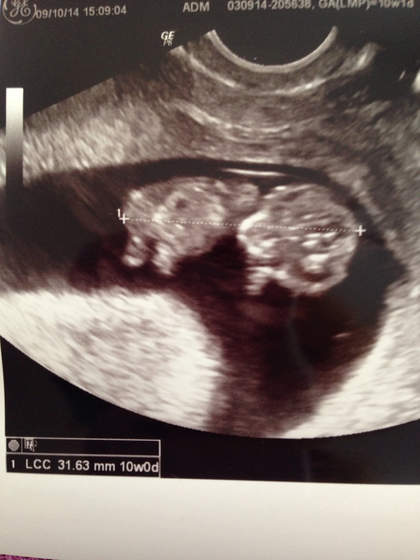

No i moja dzidzia 31.63mm 10.00 tydzień czyli zaczynam 11 wow Zobacz załącznik 647788